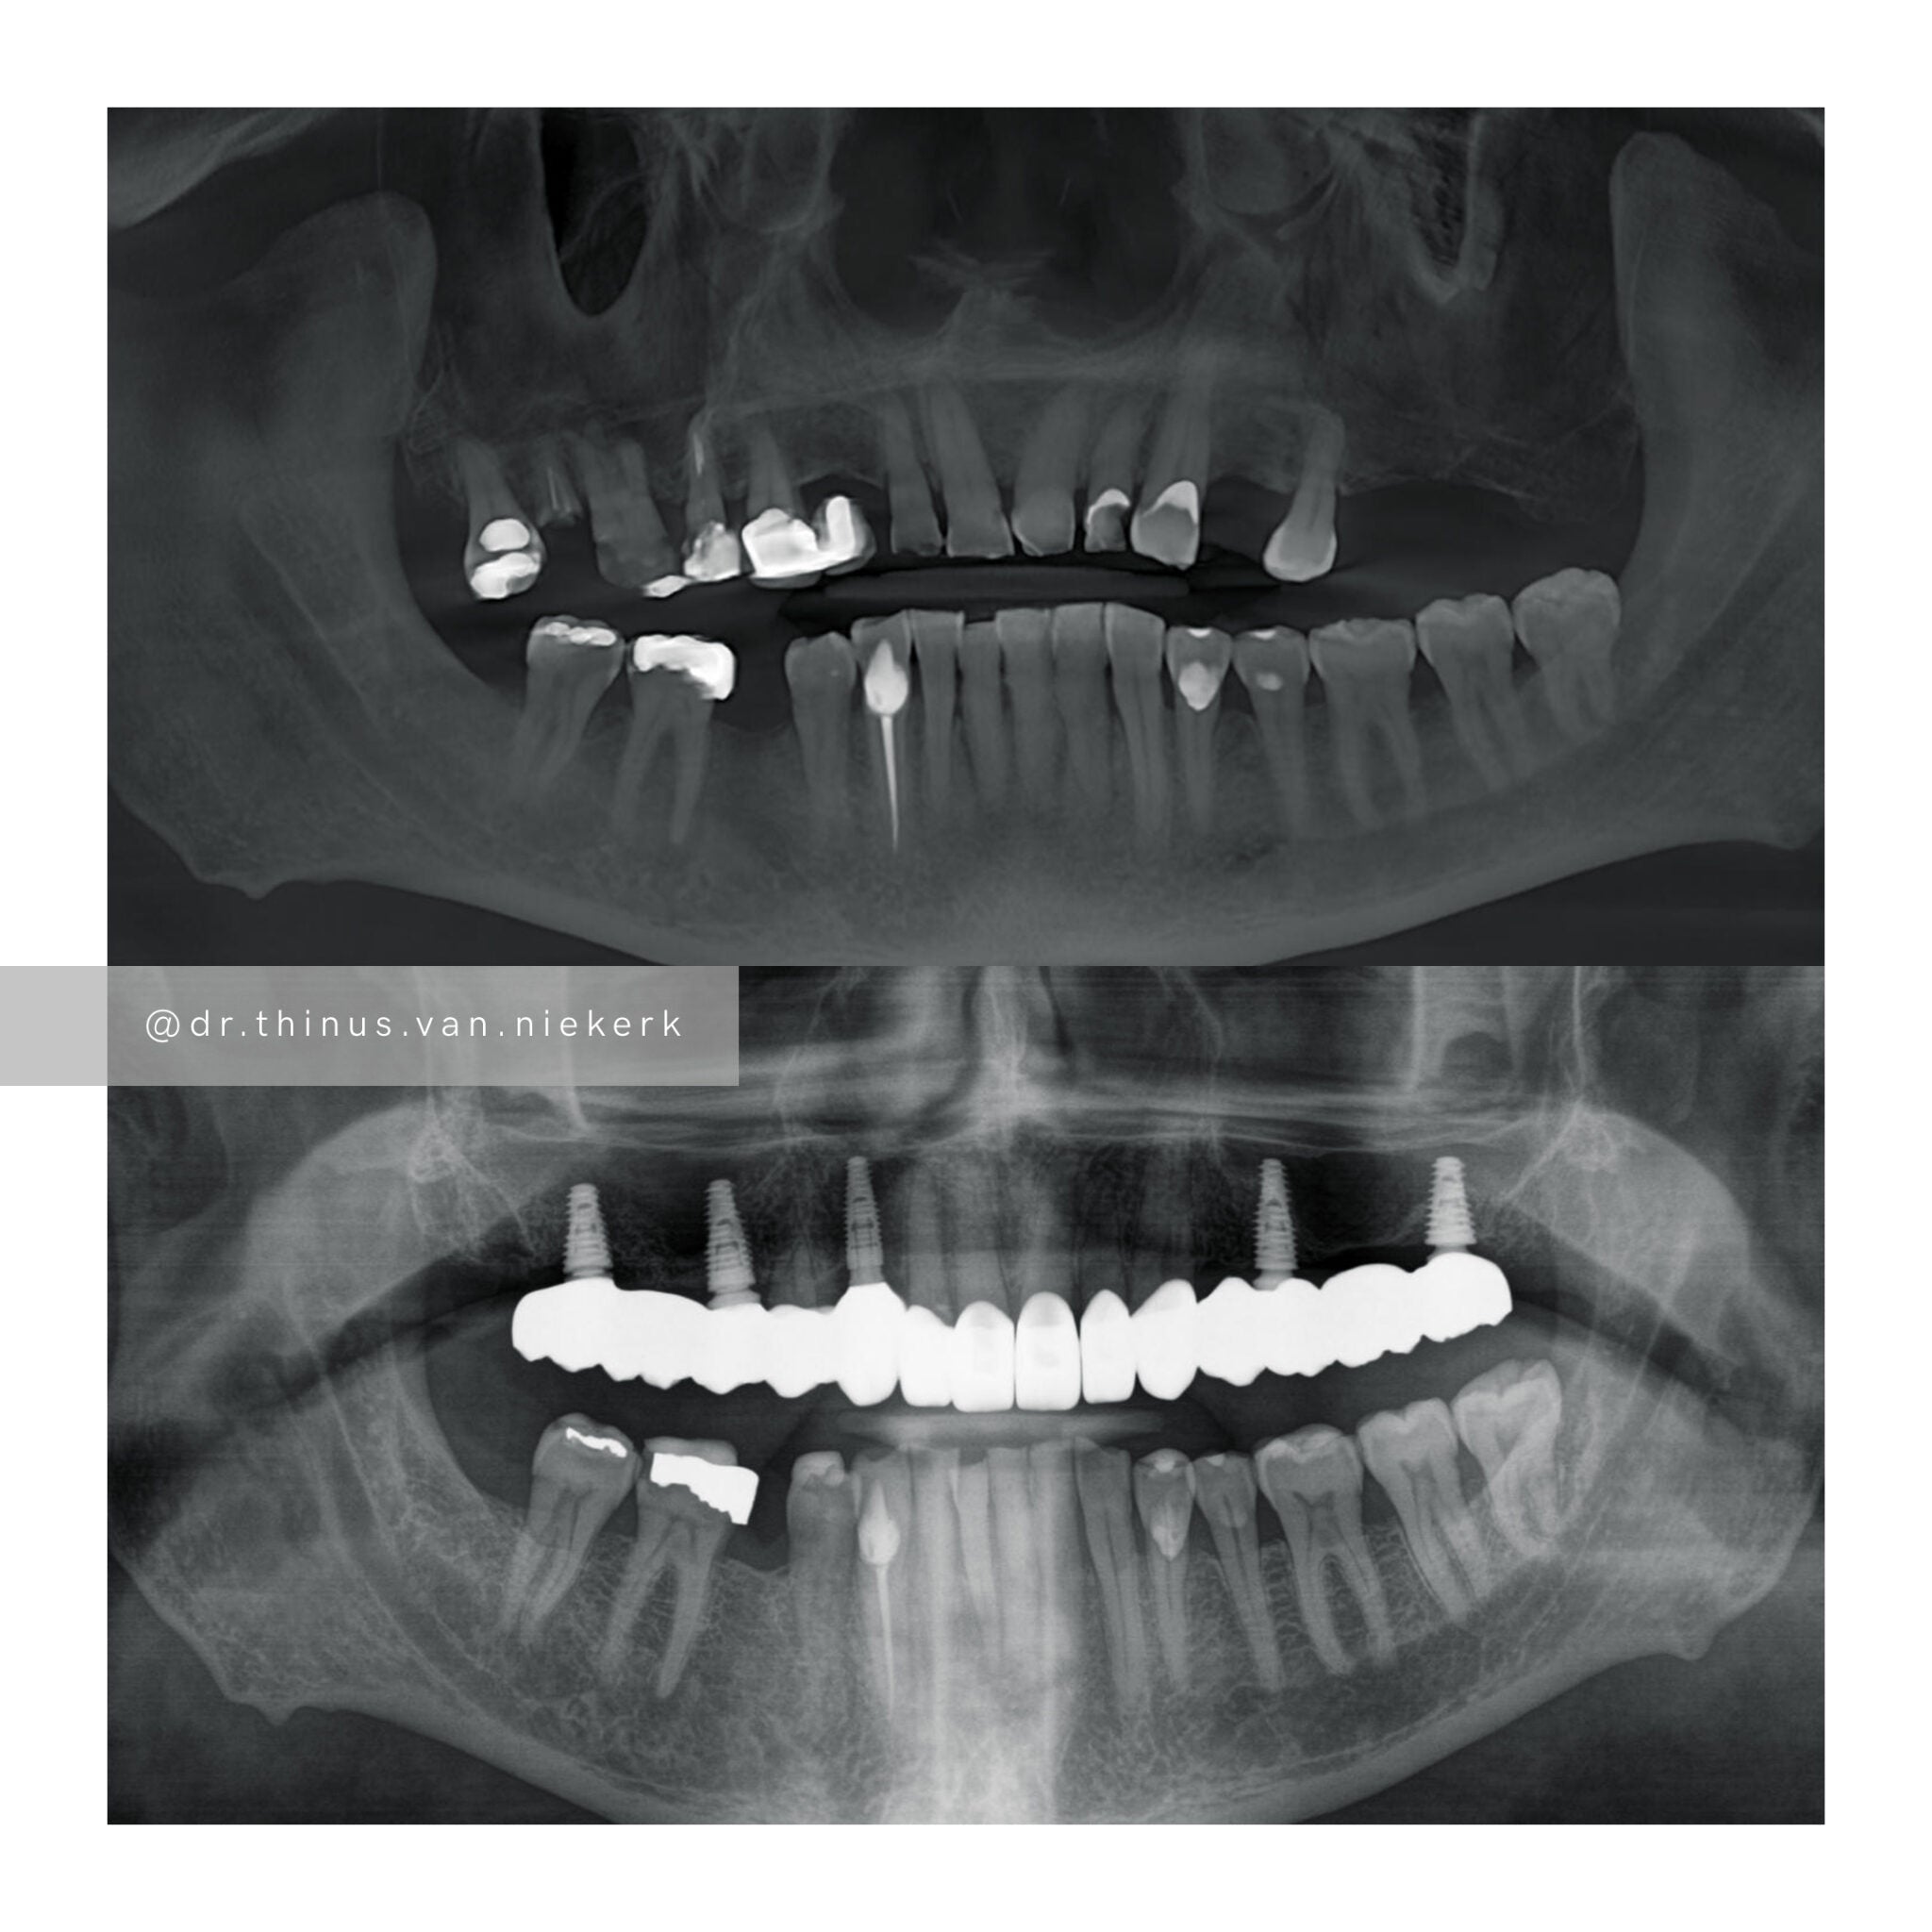

TREATMENT OBJECTIVE

Our aim was to remove all elements of infection and disease and to restore function as quickly as possible. The complete case was digitally planned prior to the day of surgery. Six fully-guided implants were placed during a two-hour morning surgery. An immediate implant-supported prosthesis was delivered on the same day.

COMMENTS

This case demonstrated the power and effectiveness of digital implant-surgery planning and CAD design software.